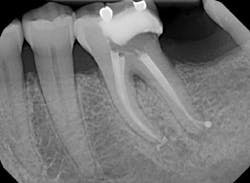

After obtaining straight line access and caries removal, the canals were located and negotiated to working length with a number 10 stainless steel C-file and Pathfiles one through three. Glidepath was confirmed with a Root ZX, with a number 15 K-file. At this time, the orifice was further enlarged and relocated over the long axis of each root with GTX 40-.10.

Next, the canals were shaped using GTX Files. Initially, a 40-.06 was taken to resistance. At this time, a crown down method was used going from 30-.06 to 20-.06. Final shape was determined to be a 30-.06 for all canals. These were confirmed using a shape verifier (provided with Guttacore obturators) and an apex locator.

Canals were irrigated with full-strength sodium hypochloride and Q-mix and agitated with an EndoActivator for one minute in each canal. Next, the canals were dried and sealer was applied with a paper point in the coronal half of the canal.

Obturation was completed by slowly placing the Guttacore obturators to length and removing the handles with a sharp spoon excavator. It can be noted that Obturation looks complete and an apical dilacerations was picked up on the distal canal.